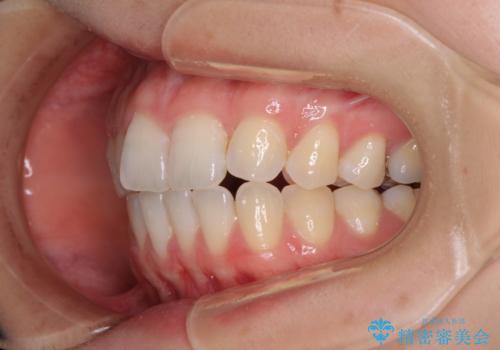

気になる上の歯を改善 インビザライン矯正

- 矯正治療の後戻りが気になるとのことで来院された患者様です。

上顎の後戻りをインビザライン・ライトで治療することとしました。

上顎のみの治療を希望されたため、咬み合わせをしっかりと改善することはできませんでしたが、審美面が大きく改善され、日常生活の機能面でも不具合を感じることはなく、大変満足していただきました。